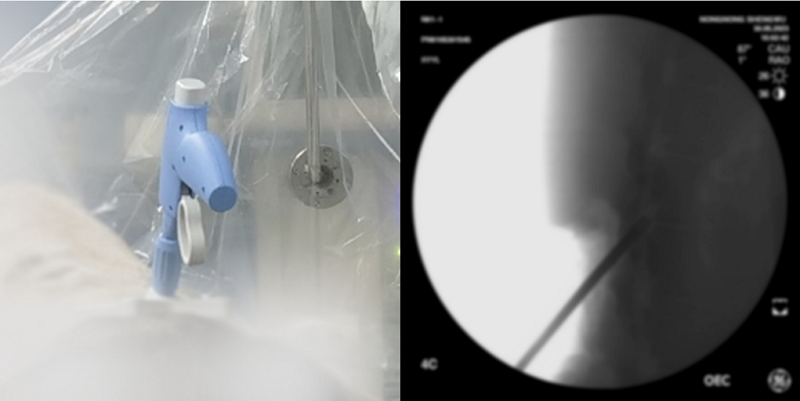

天智航“膝關(guān)節(jié)置換手術(shù)導(dǎo)航定位”系統(tǒng)通過國家藥品監(jiān)督管理局創(chuàng)新產(chǎn)品注冊申請,獲批第三類醫(yī)療器械注冊證,標(biāo)志著天智航已成為全球范圍內(nèi)第一家擁有全面覆蓋脊柱、創(chuàng)傷、關(guān)節(jié)三大骨科術(shù)式機(jī)器人產(chǎn)品的公司。